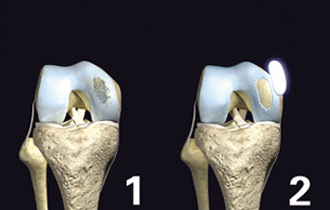

中英合资——关节动力安达(天津)生物科技有限公司是亚太地区首家以研究、生产自体软骨组织细胞移植产品为主的高科技生物企业。具有世界先进水平的自体软骨组织细胞体外培养、移植技术和产品,并拥有自主知识产权,其核心产品包括: CaReS®(软骨再生系统)、CFI(软骨栓)、NuCell(脊椎间盘修复系统)等。公司位于天津港保税区空港物流加工区环河南路,总投资2亿元人民币。

公司拥有的系列产品均采用生命科学领域细胞工程学和工程学的原理与方法,用于软骨相关疾病的治疗,适用于医疗机构骨科临床急、慢性关节软骨缺损疾病的早期修复和治愈性治疗,也可应用于脊椎间盘的软组织损伤细胞修复。是研究和开发用于修复和维护或增进人体各种组织器官损伤后功能和形态的一个边缘性新学科,属于当代前沿科学。

CaReS®(软骨再生系统)等生物组织工程技术和产品的临床应用,将为软骨缺损疾病治疗提供全新的观念并进一步丰富针对软骨缺损疾病的治疗方法,提升骨科临床的治疗水平,与世界接轨并同步发展。通过该技术和产品的临床应用,使广大的患者与欧美国家同步享受高科技生物组织工程技术与产品带来的福祉,提高生活质量,造福于社会。